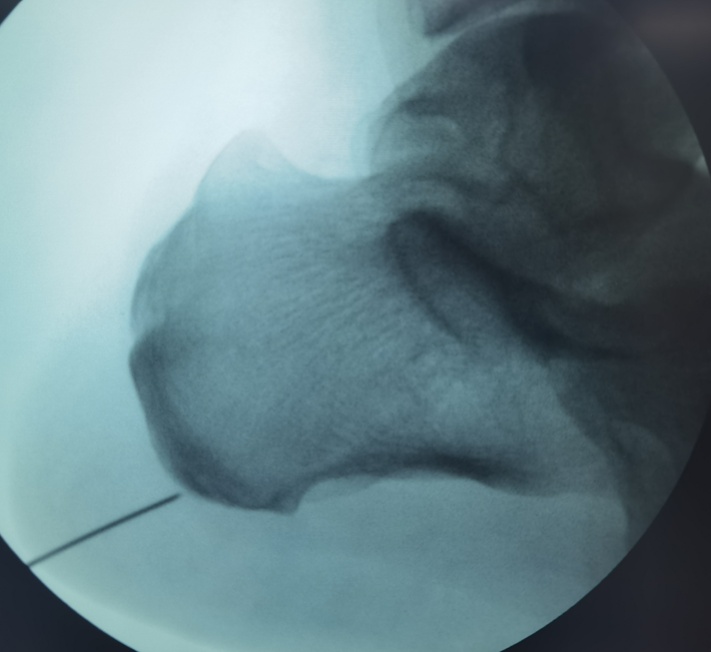

对于这类顽固性足跟痛患者,神经射频消融术提供了一个微创选择。它不是传统意义上的“大手术”,也不是把脚底切开,而是在精准定位下,用很细的射频针作用于疼痛相关神经靶点,减轻疼痛信号传导,从而达到镇痛效果。

69岁的朱先生,左足跟疼痛已有一年,近1个半月症状加重,尝试过多种保守治疗,疼痛始终没有明显缓解。后来接受了我院关节外科的神经射频消融术治疗,整个过程不到半小时,术后疼痛得到了很大缓解,生活状态也明显改善了。